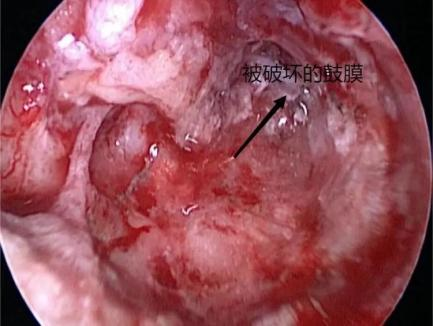

第二天,耳鼻喉科团队为患儿行急诊手术。在行气管插管全麻后,由副主任医师张金平在旁指导、主治医师谢记发主刀下,通过耳内镜下观察,见外耳道深部一不规则石头,已进入鼓室腔,完全阻塞鼓室内结构,外耳道黏膜部分缺损,外耳道骨质裸露,碰触石头,见缝隙处有少量脓液溢出。

耳内镜下初步对异物情况进行判断,不可能直接取出。遂启动第二方案,微创行耳内切口,扩大术腔,磨除外耳道骨质,扩大外耳道。因石头棱角较多,主刀医生边松动石头边磨除棱角处骨质,小心旋转角度,向外用力终于取出约6.6mm×4.3mm的异物。

术后患儿安全返回病房,予以加强抗炎治疗,患儿无右耳痛、出血,眩晕逐渐减轻。待鼓室及外耳道黏膜恢复正常,再择日行鼓膜修补或同期行人工听骨听力重建术。病情稳定后,患儿于术后第4天出院。